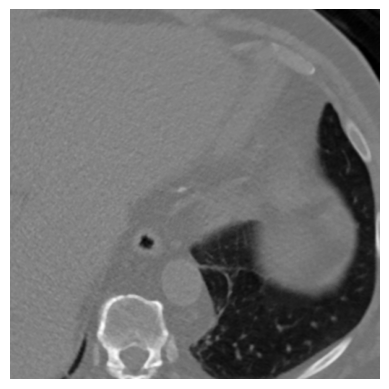

The effectiveness of our label-guided approach is visualized in Figure 4, which compares feature representations generated by standard DINO and DINO-LG models via PCA analysis. The figure shows an original CT slice containing coronary calcification in the left anterior descending artery (a), where the ground truth annotation (b) occupies approximately 0.04% of the image area. Standard DINO features (c) exhibit diffuse activation across cardiac structures, while DINO-LG features (d) demonstrate concentrated activation on calcified regions (bright yellow areas), validating successful feature guidance toward regions of clinical interest. The PCA visualization is applied to 768-dimensional [CLS] token embeddings extracted from the final transformer layer to illustrate how label-guided training directs the model’s attention to task-relevant features.

(a)

(b)

(c)

(d)

Figure 4: Feature visualization comparison via PCA. (a) Original CT slice. (b) Ground truth annotation. (c) Standard DINO features. (d) DINO-LG features.